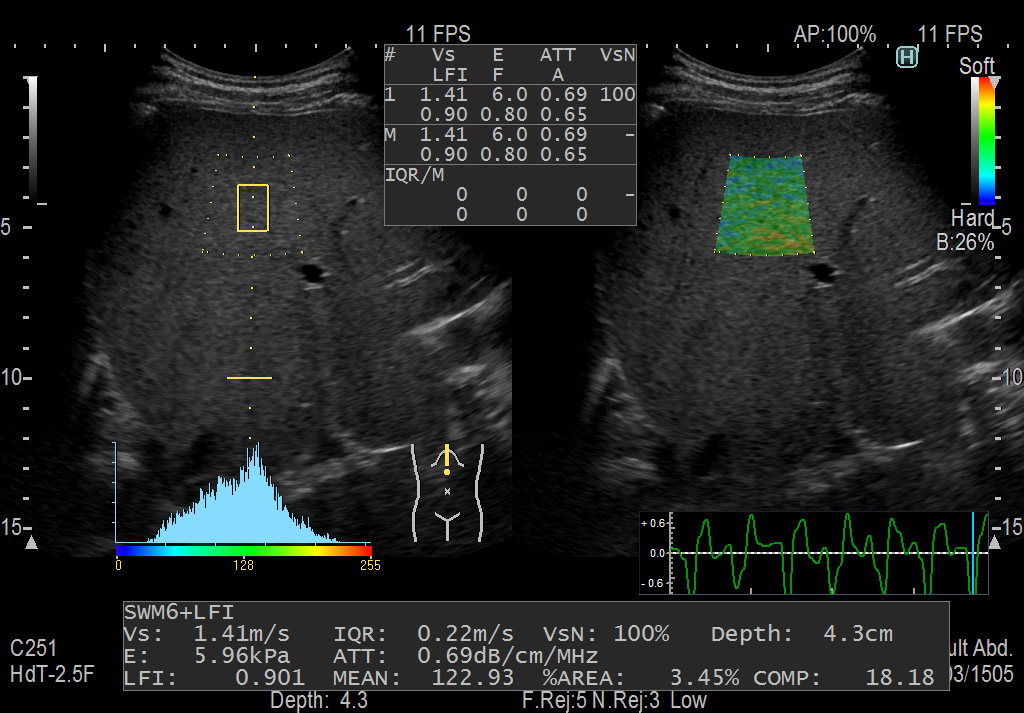

Печень. В режиме Combi-Elasto методы RTE и SWM применяются одновременно